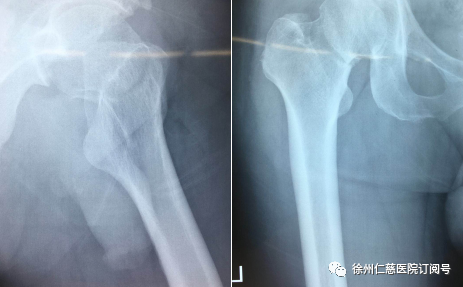

任主任介绍,4月12日,马师傅因骑电动车摔倒导致左股骨颈骨折,左下肢屈曲外旋畸形,左髋部肿胀,左髋关节活动受限,不能下地走路。专家团队诊断后,认为马师傅适应证非常明确,当即决定为马师傅进行机器人手术。

上午10时许,手术团队的新“同事”——“天玑”骨科机器人准备就绪,手术正式开始。10多分钟后,手术团队将形如“天线”的示踪器安装在患者手术处,使用机器人透视下取得股骨颈图像,在电脑上规划空心钉方向,规划完成后由机器人进行精准定位,沿定位套筒置入克氏针固定,透视见克氏针位置及长短适中,依次置入3枚股骨颈空心螺钉固定,再次行C型臂透视正侧位见骨折对位对线良好,螺钉位置以及长短均适中,经过1小时20分钟,机器人手术顺利结束。